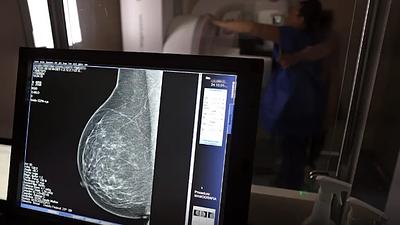

Super Centro usa IA em diagnósticos de câncer de mama

Os laudos dos exames de mamografia realizados no Centro Carioca de Diagnóstico e Tratamento por Imagem (CCDTI) são avaliados e assinados por profissionais médicos capacitados, no entanto, a IA auxilia na identificação de possíveis lesões difíceis de serem vistas.